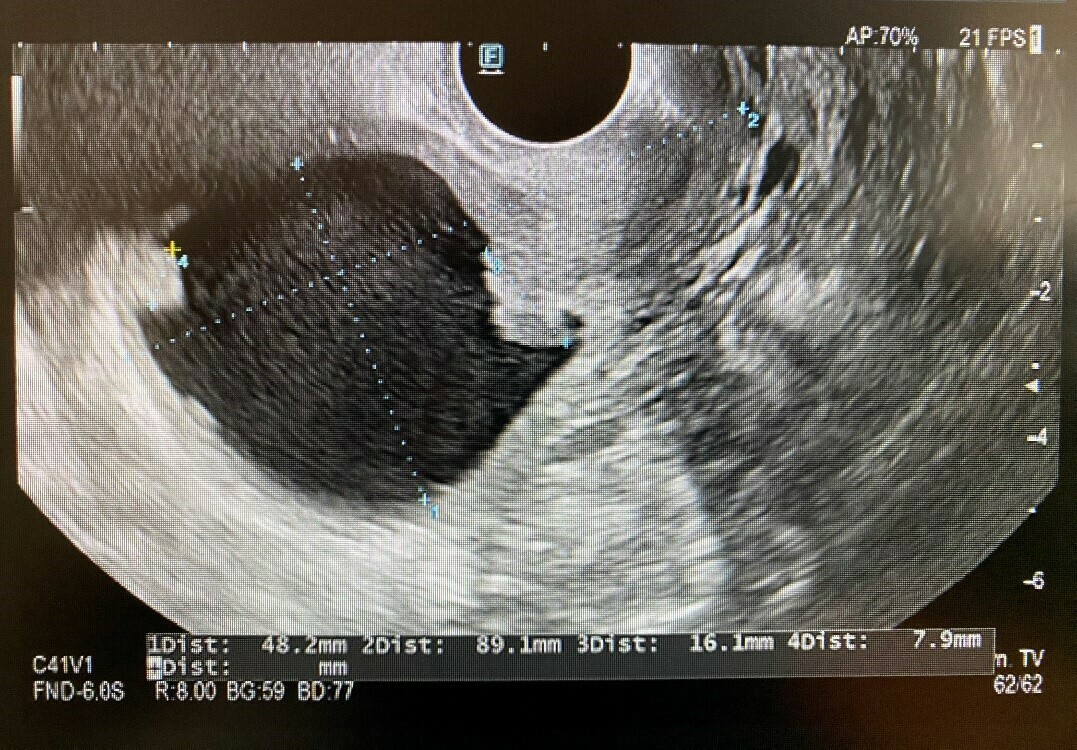

Treatment success is correlated with stage of the disease, histological grade and type of tumor; accordingly, timely detection of this disease is critical [3]. Toward this end, a transvaginal ultrasound examination and doppler flow are performed [3, 4, 5] (Fig. 2). Other than this method, there currently exists no sufficient screening technique or specific laboratory analysis to establish a diagnosis of endometrial cancer prior to the onset of symptoms.

Fig. 2.Transvaginal ultrasound endometrial carcinoma the International Federation of Gynecology and Obstetrics (FIGO) IA (Dr Branko Andrić, Department for Women’s Health Care, Health Center Raska, Raska). 1Dist: 48.2 mm (distended uterine cavity), 2Dist: 89.1 mm (uterus length), 3Dist: 16.1 mm (carcinoma endometrii), 4Dist: 7.9 mm (carcinoma endometrii).